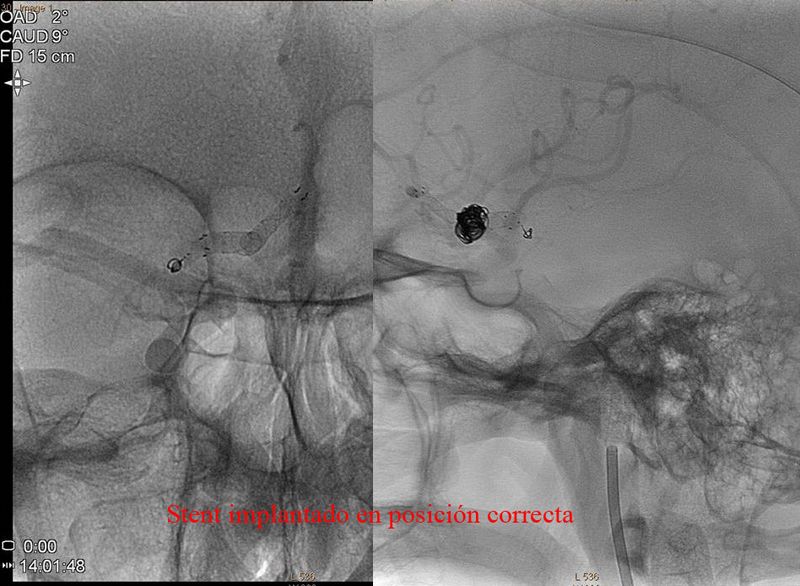

Aneurisma de arteria comunicante anterior